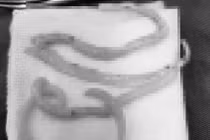

Bệnh nhân khỏe mạnh đi khám sức khỏe định kỳ phát hiện giun đũa trong đại tràng. Thói quen ăn gỏi cá, rau sống thường xuyên, có thể thông qua đó bệnh nhân đã vô tình đưa ấu trùng trứng giun vào trong bụng.